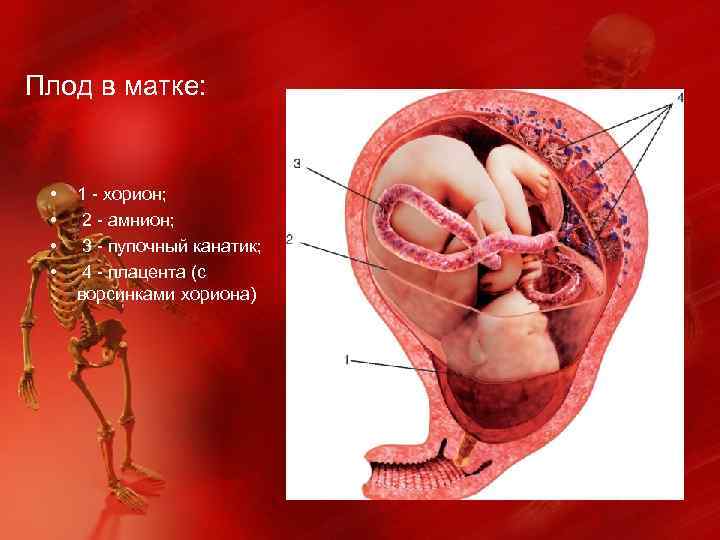

Околоплодный пузырь и плацента: структура и функции